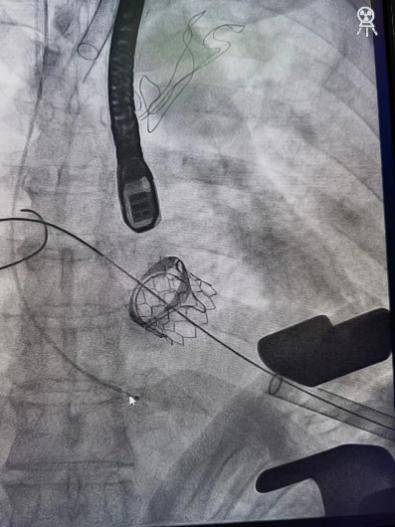

9:00 , 常规手术患者已开始手术 。 微创多瓣膜置换、冠状动脉搭桥术、经心尖介入二尖瓣瓣中瓣术……手术台上医生细致、耐心 , 另一边多名需要急诊救治的危重患者也同时在准备和手术中 。